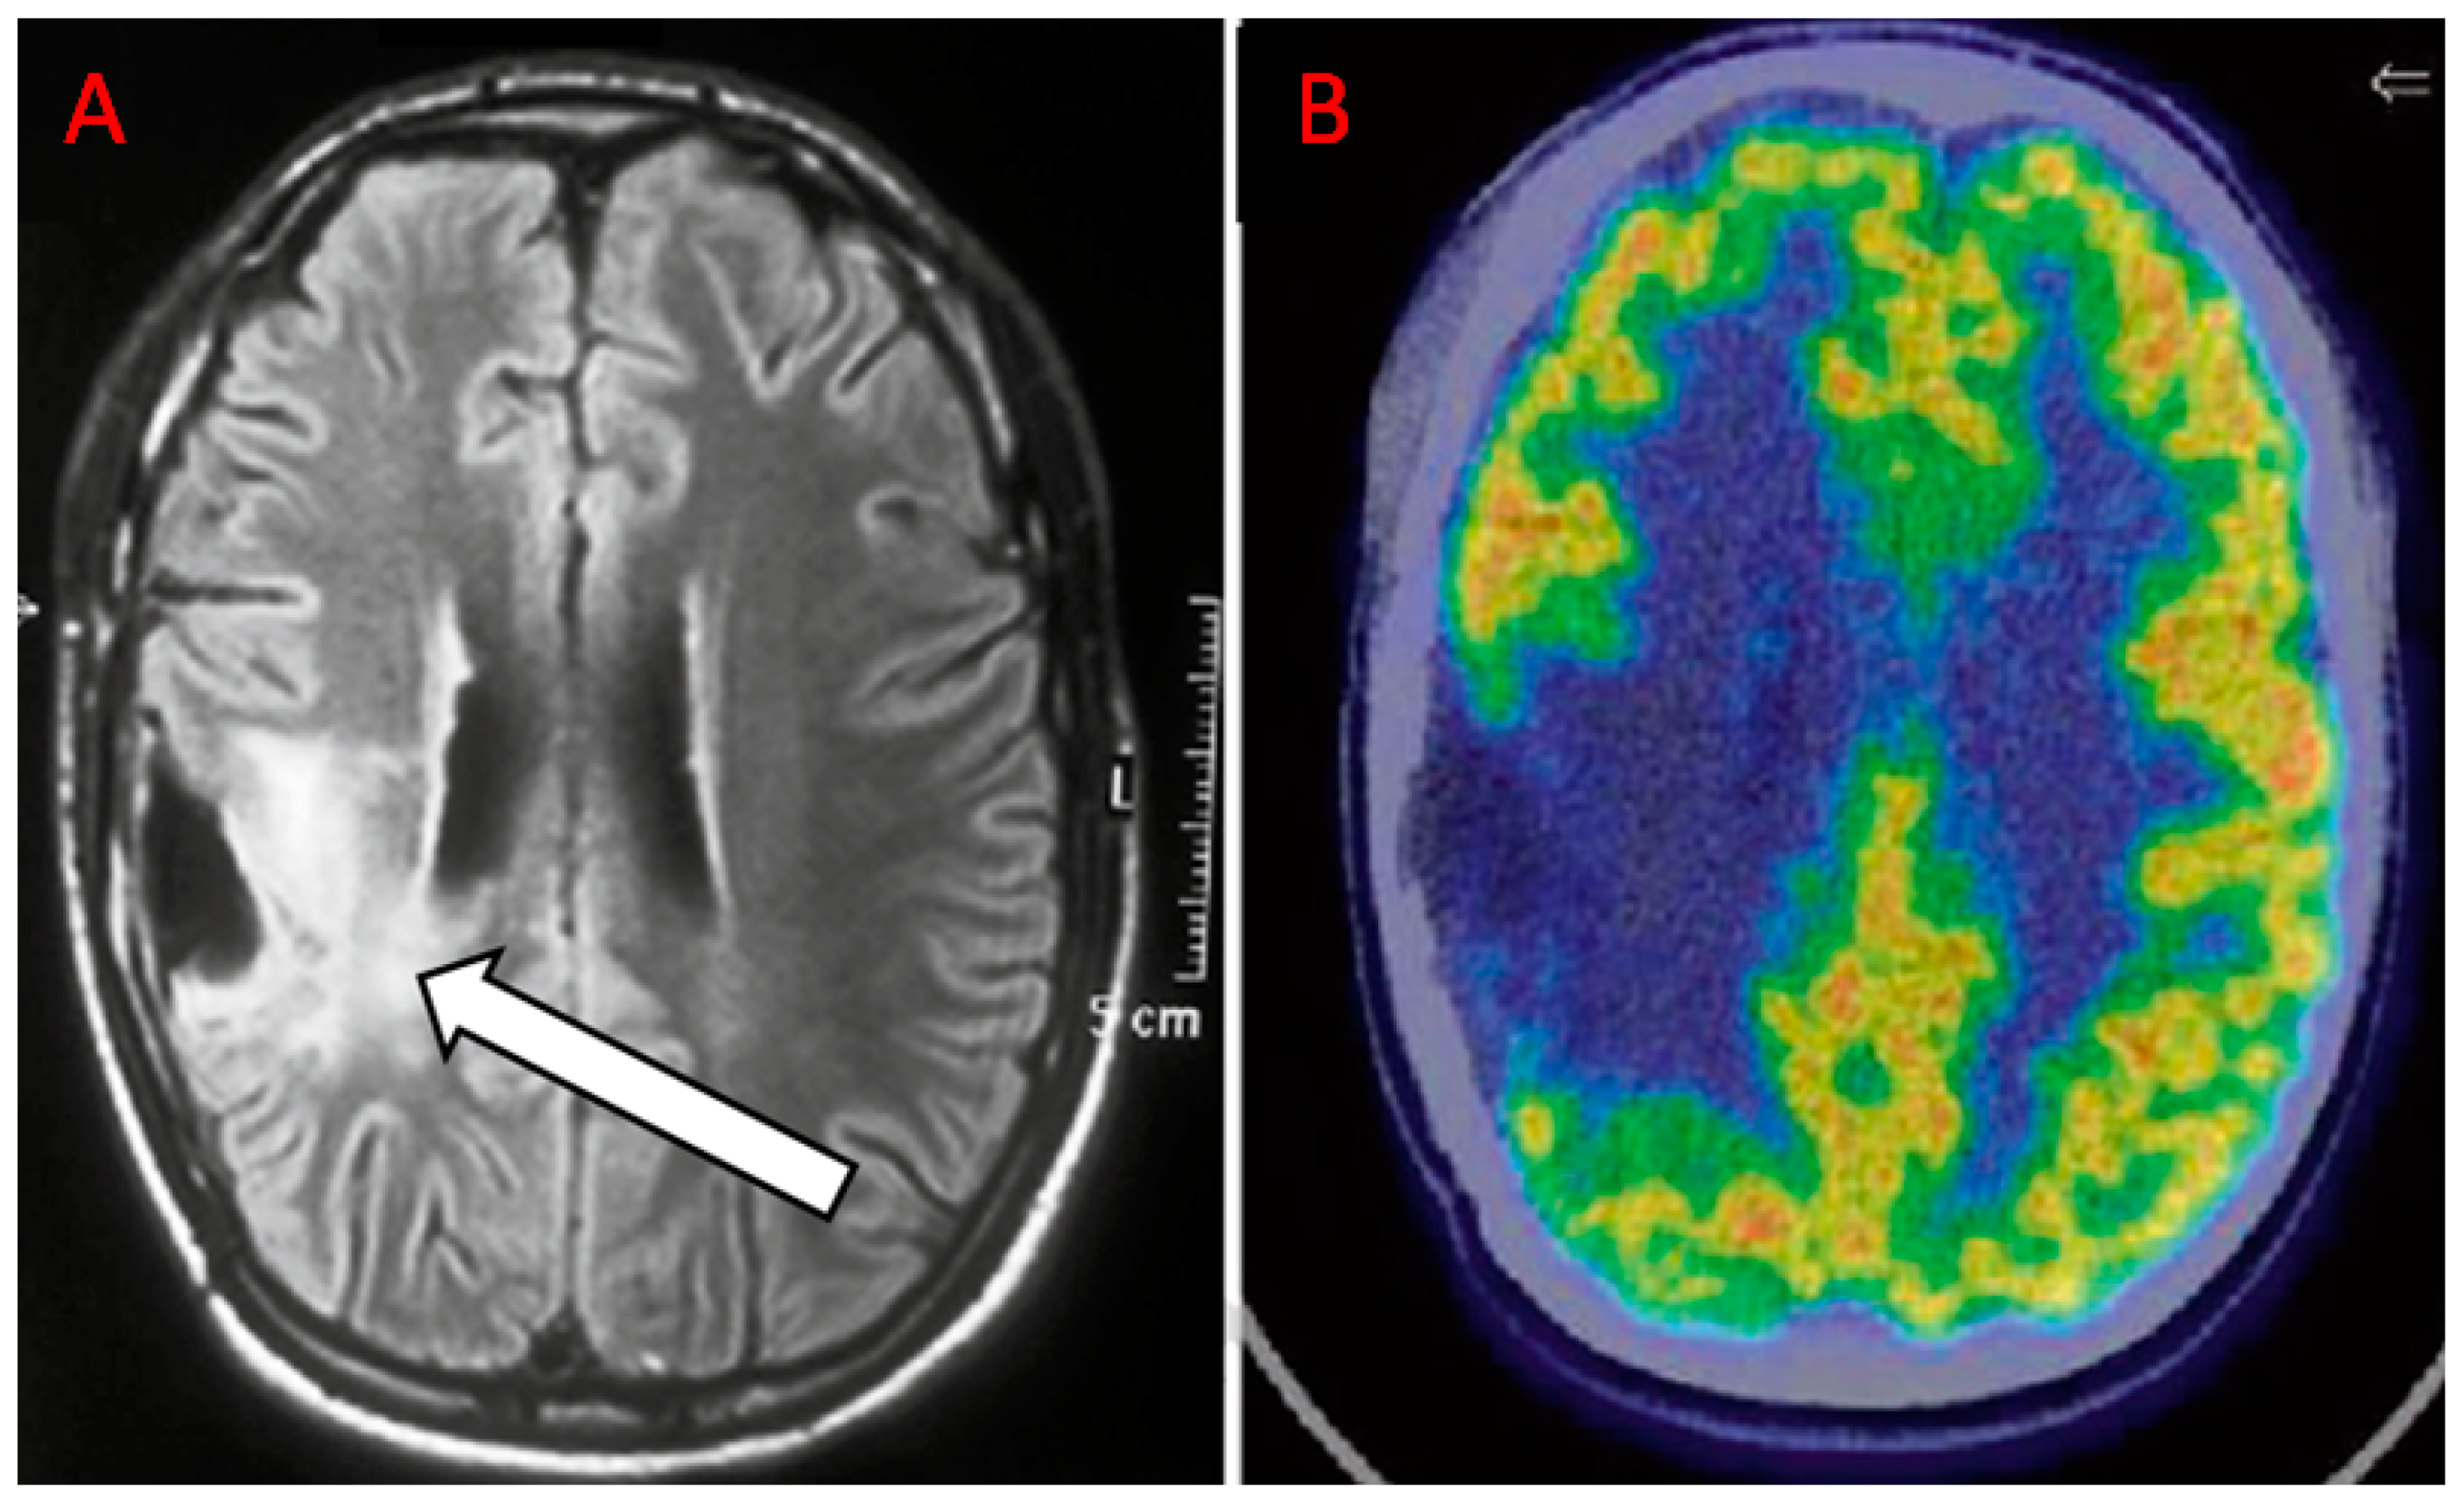

- Kinoshita, M.; Arita, H.; Goto, T.; Okita, Y.; Isohashi, K.; Watabe, T.; Kagawa, N.; Fujimoto, Y.; Kishima, H.; Shimosegawa, E.; et al. A novel pet index, 18f-fdg-11c-methionine uptake decoupling score, reflects glioma cell infiltration. J. Nucl. Med. 2012, 53, 1701–1708. [Google Scholar] [CrossRef]